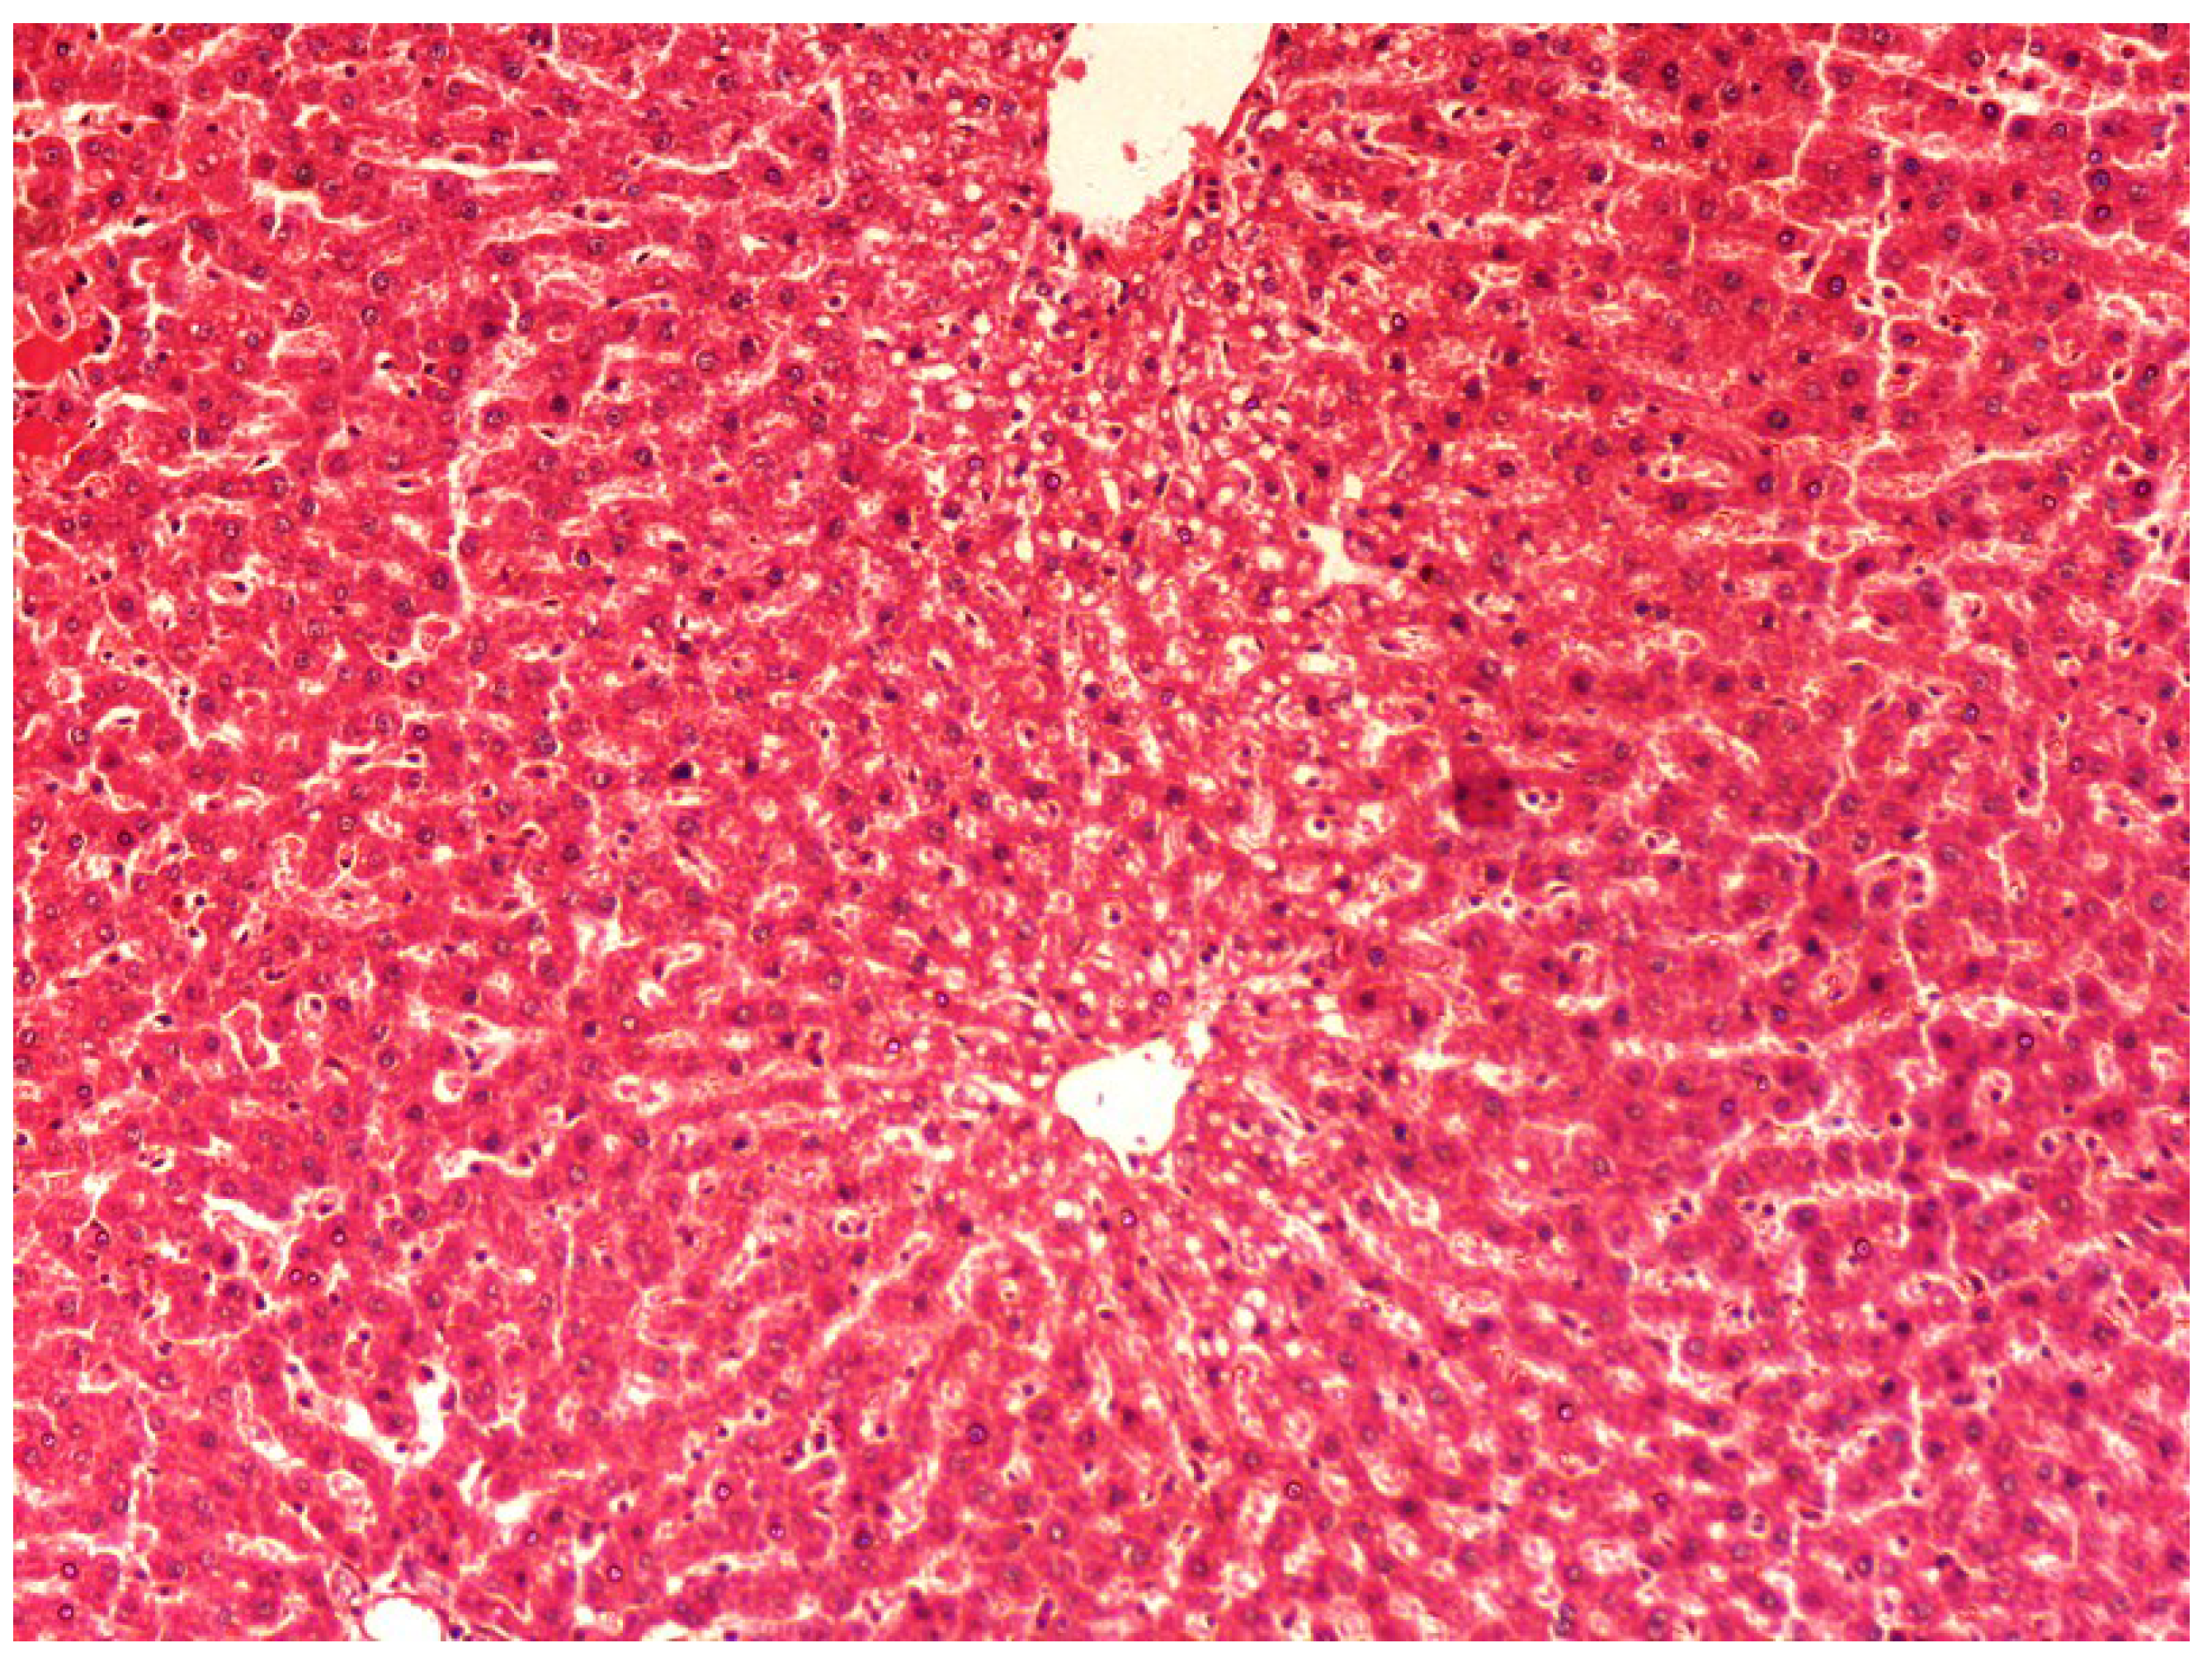

The histopathology of CCl4-induced rats when compared to normal hepatic architecture (Figure 2) showed massive fatty changes, necrosis, ballooning degeneration and the loss of cellular boundaries (Figure 3). The liver sections of plumieride at the dose level of 5 mg/kg body weight plus CCl4-treated rats (Group III) showed mild prevention of CCl4-induced degenerative changes with the few pyknotic nuclei and fatty vacuolizations in the cytoplasm (Figure 4). The liver sections of plumieride treated rats at the dose level of 10 mg/kg body weight along with CCl4 (Group IV) indicated partial amelioration of degenerative effects in hepatocytes but still show cloudy swelling and mild fatty changes (Figure 5). The histomorphological picture of liver sections of plumieride at the dose level of 20 mg/kg body weight along with CCl4-induction to rats (Group V) showed more or less normal labular patterns devoid of degenerative changes, and cytoplasm was preserved with prominent nucleus without intracellular lipid accumulation (Figure 6) almost comparable to the normal control and silymarin treated Group VI (Figure 7).

Figure 2.

Photomicrograph of control rat liver section showing well brought central vein, hepatic cells with preserved cytoplasm and prominent nucleus at H & E × 10.